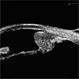

- Lacteocrumenasia, ultrasound biomicroscopy

- Ultrasonography device

- A 75-year-old female with a history of cataract surgery with intraocular lens implantation 20 years ago presented with progressive visual loss. On slit lamp examination, opaque material was found in the capsular bag behind the intraocular lens. Ultrasound biomicroscopy revealed hyperechoic material contained in the temporal-posterior sector of the capsular bag corresponding to lacteocrumenasia.